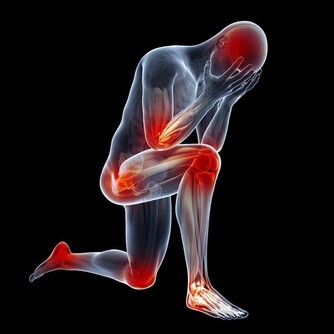

相信大家都不想痛風發作,不僅是因為那滋味太痛苦了,還因為它會帶來各種並發症,比如說關節疼痛,嚴重的甚至會變形,不能正常活動關節。若是尿酸結晶沉積在腎小管裡,還有可能損傷腎臟,形成結石,給身體加上另一重痛苦。

張大伯幾年前做了心臟支架手術,每天都要服用阿司匹林,就這樣吃了很長時間,他突然發現自己的腳趾關節疼痛難忍,還有點發紅,自己也沒犯飲食忌諱,怎麼痛風發作了呢?家人趕緊帶張大伯到醫院檢查。